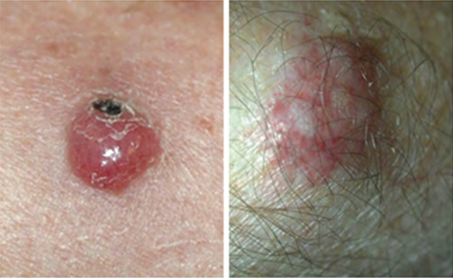

Basal Cell Carcinoma (BCC) Photos

Basal cell carcinoma presenting as a pink growth. Photo: International Skin Imaging Collaboration at isic-archive.com

A small pink growth with a slightly raised, rolled edge and a crusted indentation in the center. (BCC)